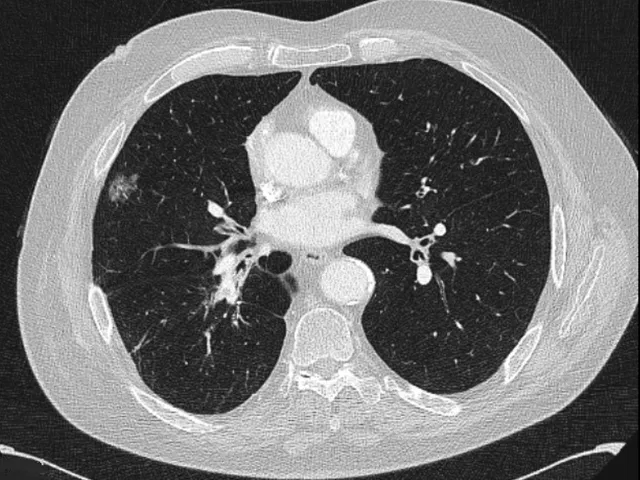

This diagnostic imaging in lung cancer reporting module is aimed at radiologists, but also medical oncologists, radiation oncologists, and pulmonologists who are interested in improving their clinical skills with regard to the interpretation and identification of images in the diagnosis, staging and response assessment of cases of lung cancer, principally using CT. Some cases with PET or MRI will also be shown.

- Recognise the thoracic anatomy required to perform a correct TNM and staging classification for lung cancer

- Recognise the essential findings that can influence the various therapeutic options